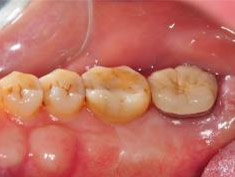

牙周初診時患者之口內觀。口內明顯牙菌斑及牙結石堆積。全口嚴重牙齦紅腫。治療前X光片。#37的近心側有較深的骨內缺損,剩餘齒槽骨高度只有20%。

第一階段牙周基本治療後,牙齦發炎狀況明顯獲得改善。